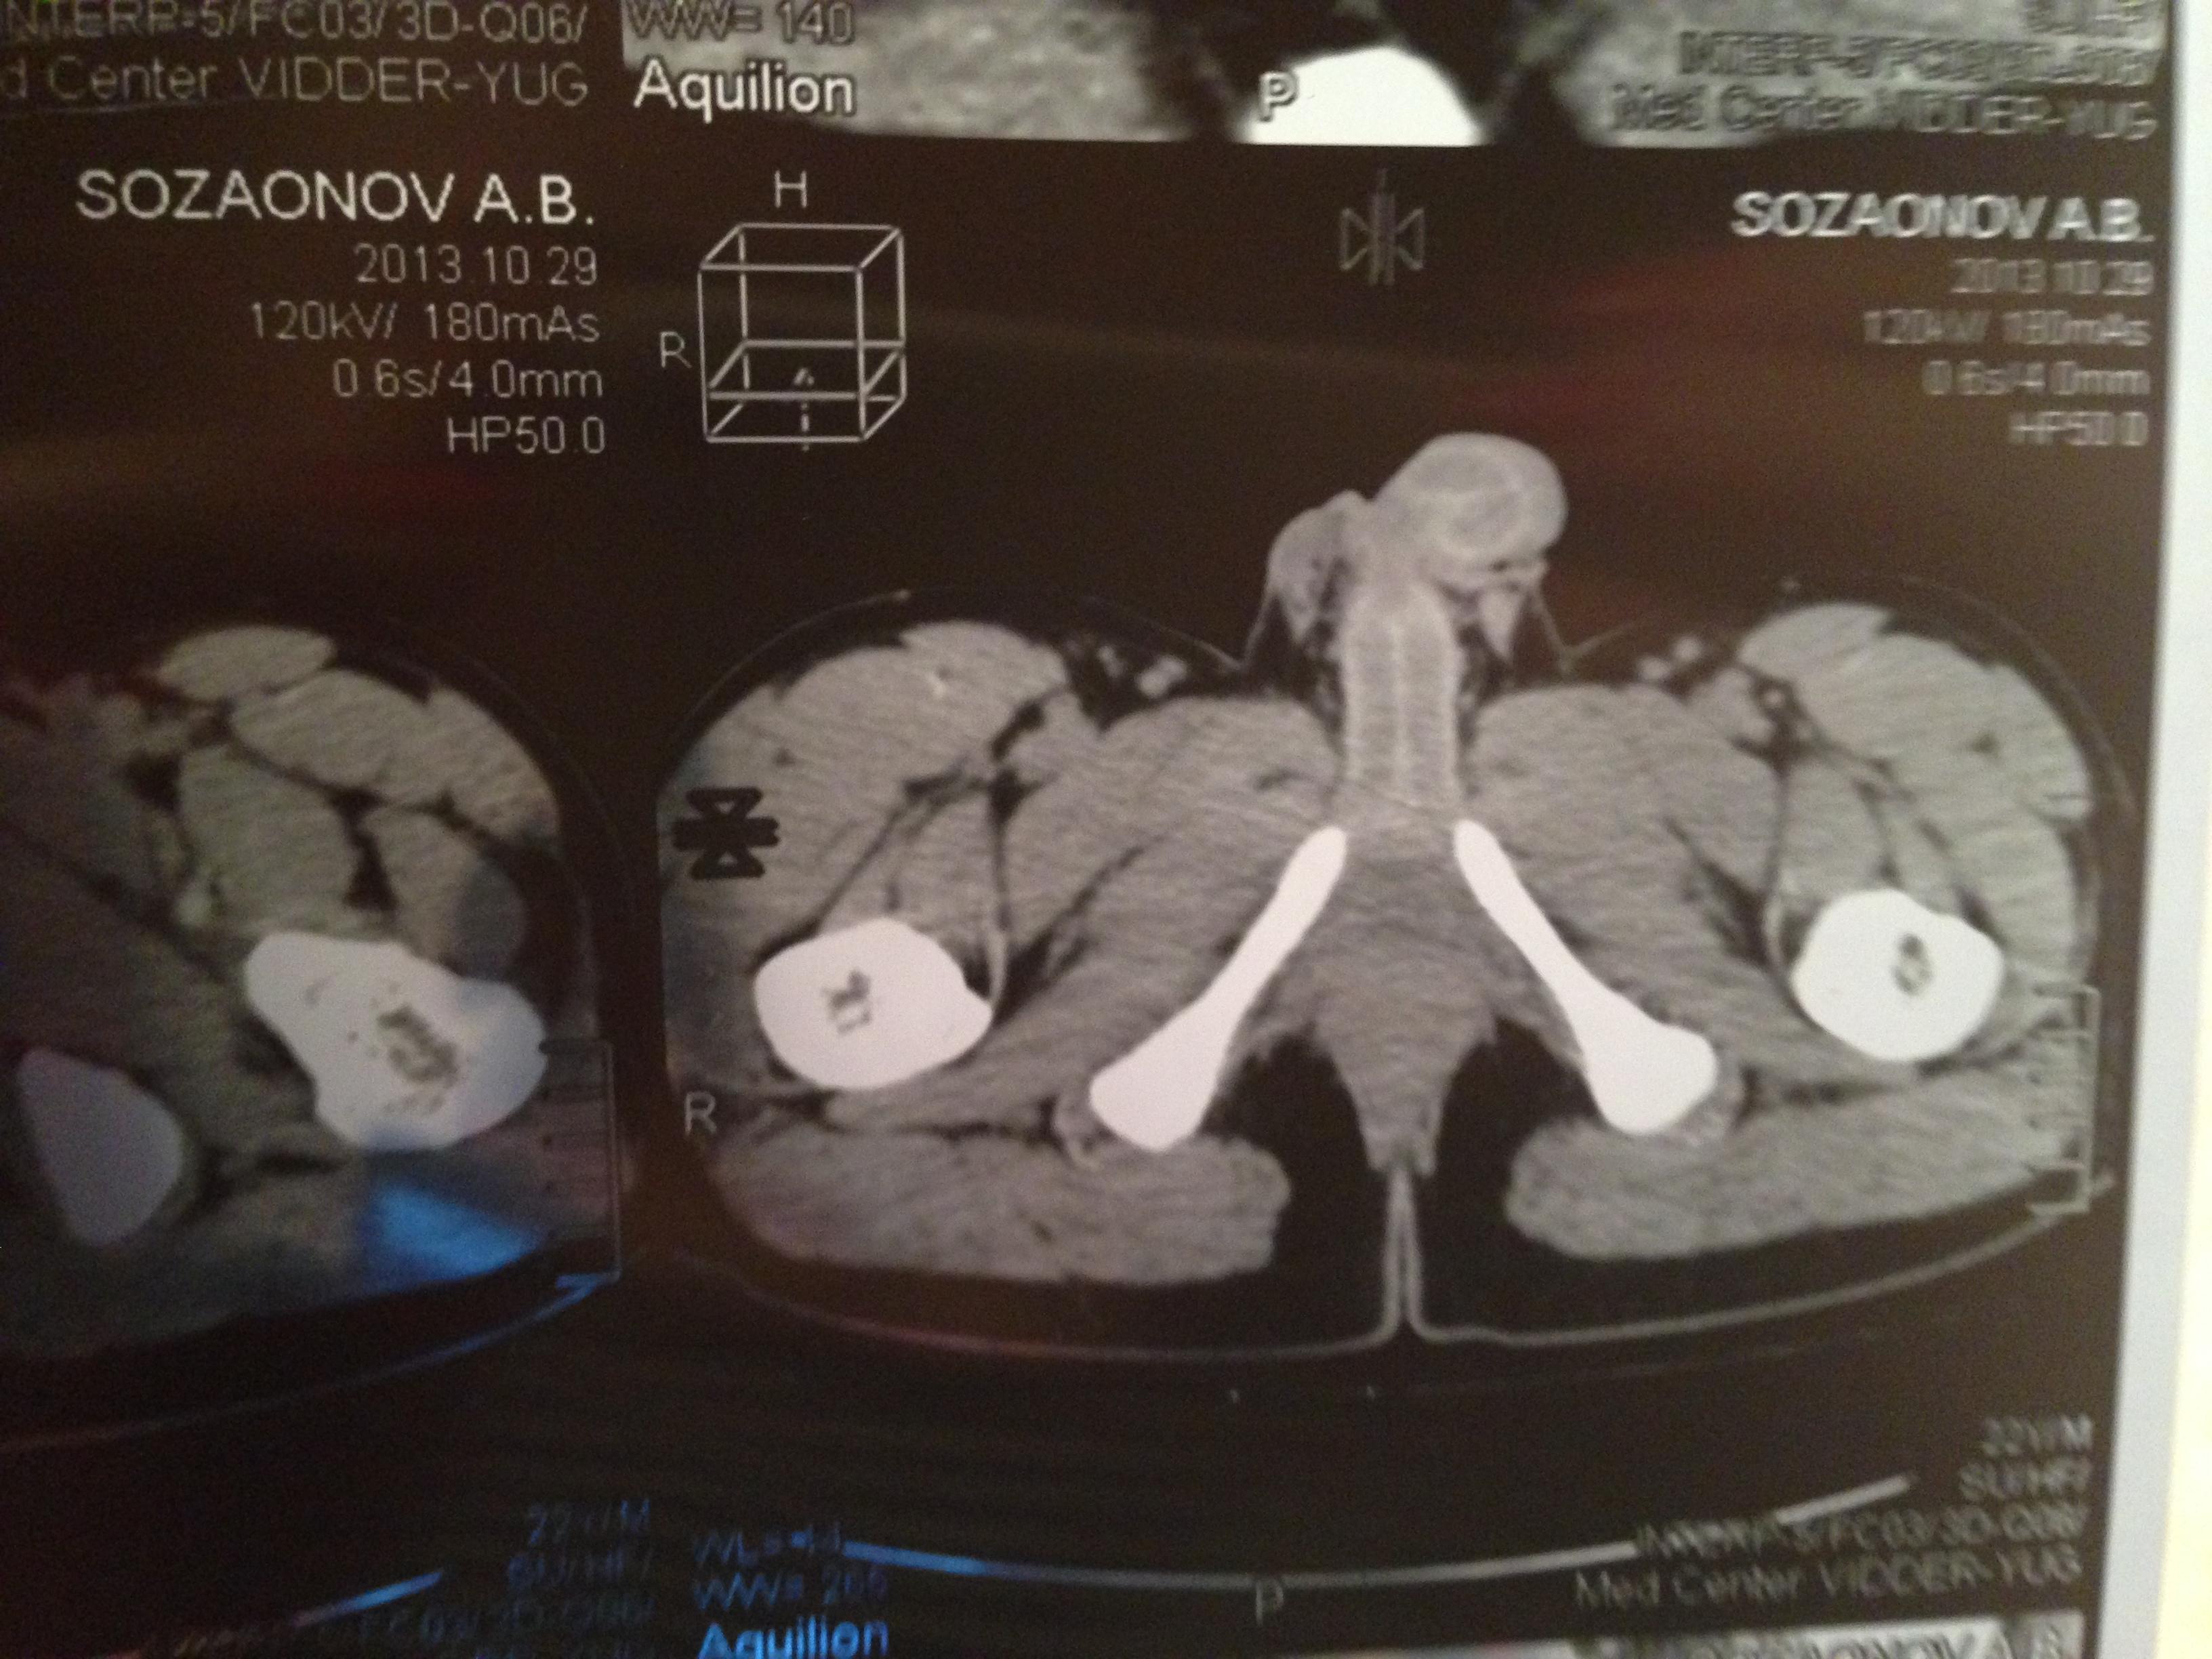

проведена МСКТ области таза!Внеорганных дополнительных патологических образований,лимфаденопатии или свободной жидкости в области таза не выявлено.

Мочевой пузырь-наполнен,стенки не утолщенны,паравезикально-без грубой органки.

Граница между предстательной железой и пузырем несколько четкая,контур пузыря на данном уровне не деформирован.

Предстательная железа-без грубой органики,еденичные микрокальцинаты.

Семенные пузырьки-конфигурация не совсем типична,примерный размер правого 26*28мм.Отмечаются признаки кистовидной трансформации и микрокальцинации обоих пузырьков.Наибольшая из кист слева достигает 9 мм.Обращает на себя внимание неравномерная кальцинация стенок крупных регионарных(текстикулярных)артерий с обоих сторон.

Костно-деструктивных изменений характерных для mts со стороны костей таза не отмечено.

Параректальная клетчатка-не изменена,патологически увеличенных лимфоузлов в параректальном пространстве не отмечено.M.m.levator ani-без особенностей.

Заключение:на момент исследования,КТ-данных за наличие внеорганных дополнительных патологических образований,лимфоденопатии или свободной жидкости в области таза не выявлено.КТ-признаки в пользу проявлений калькулезного везикулита с элементами кистовидной трансформации семенных пузырьков.